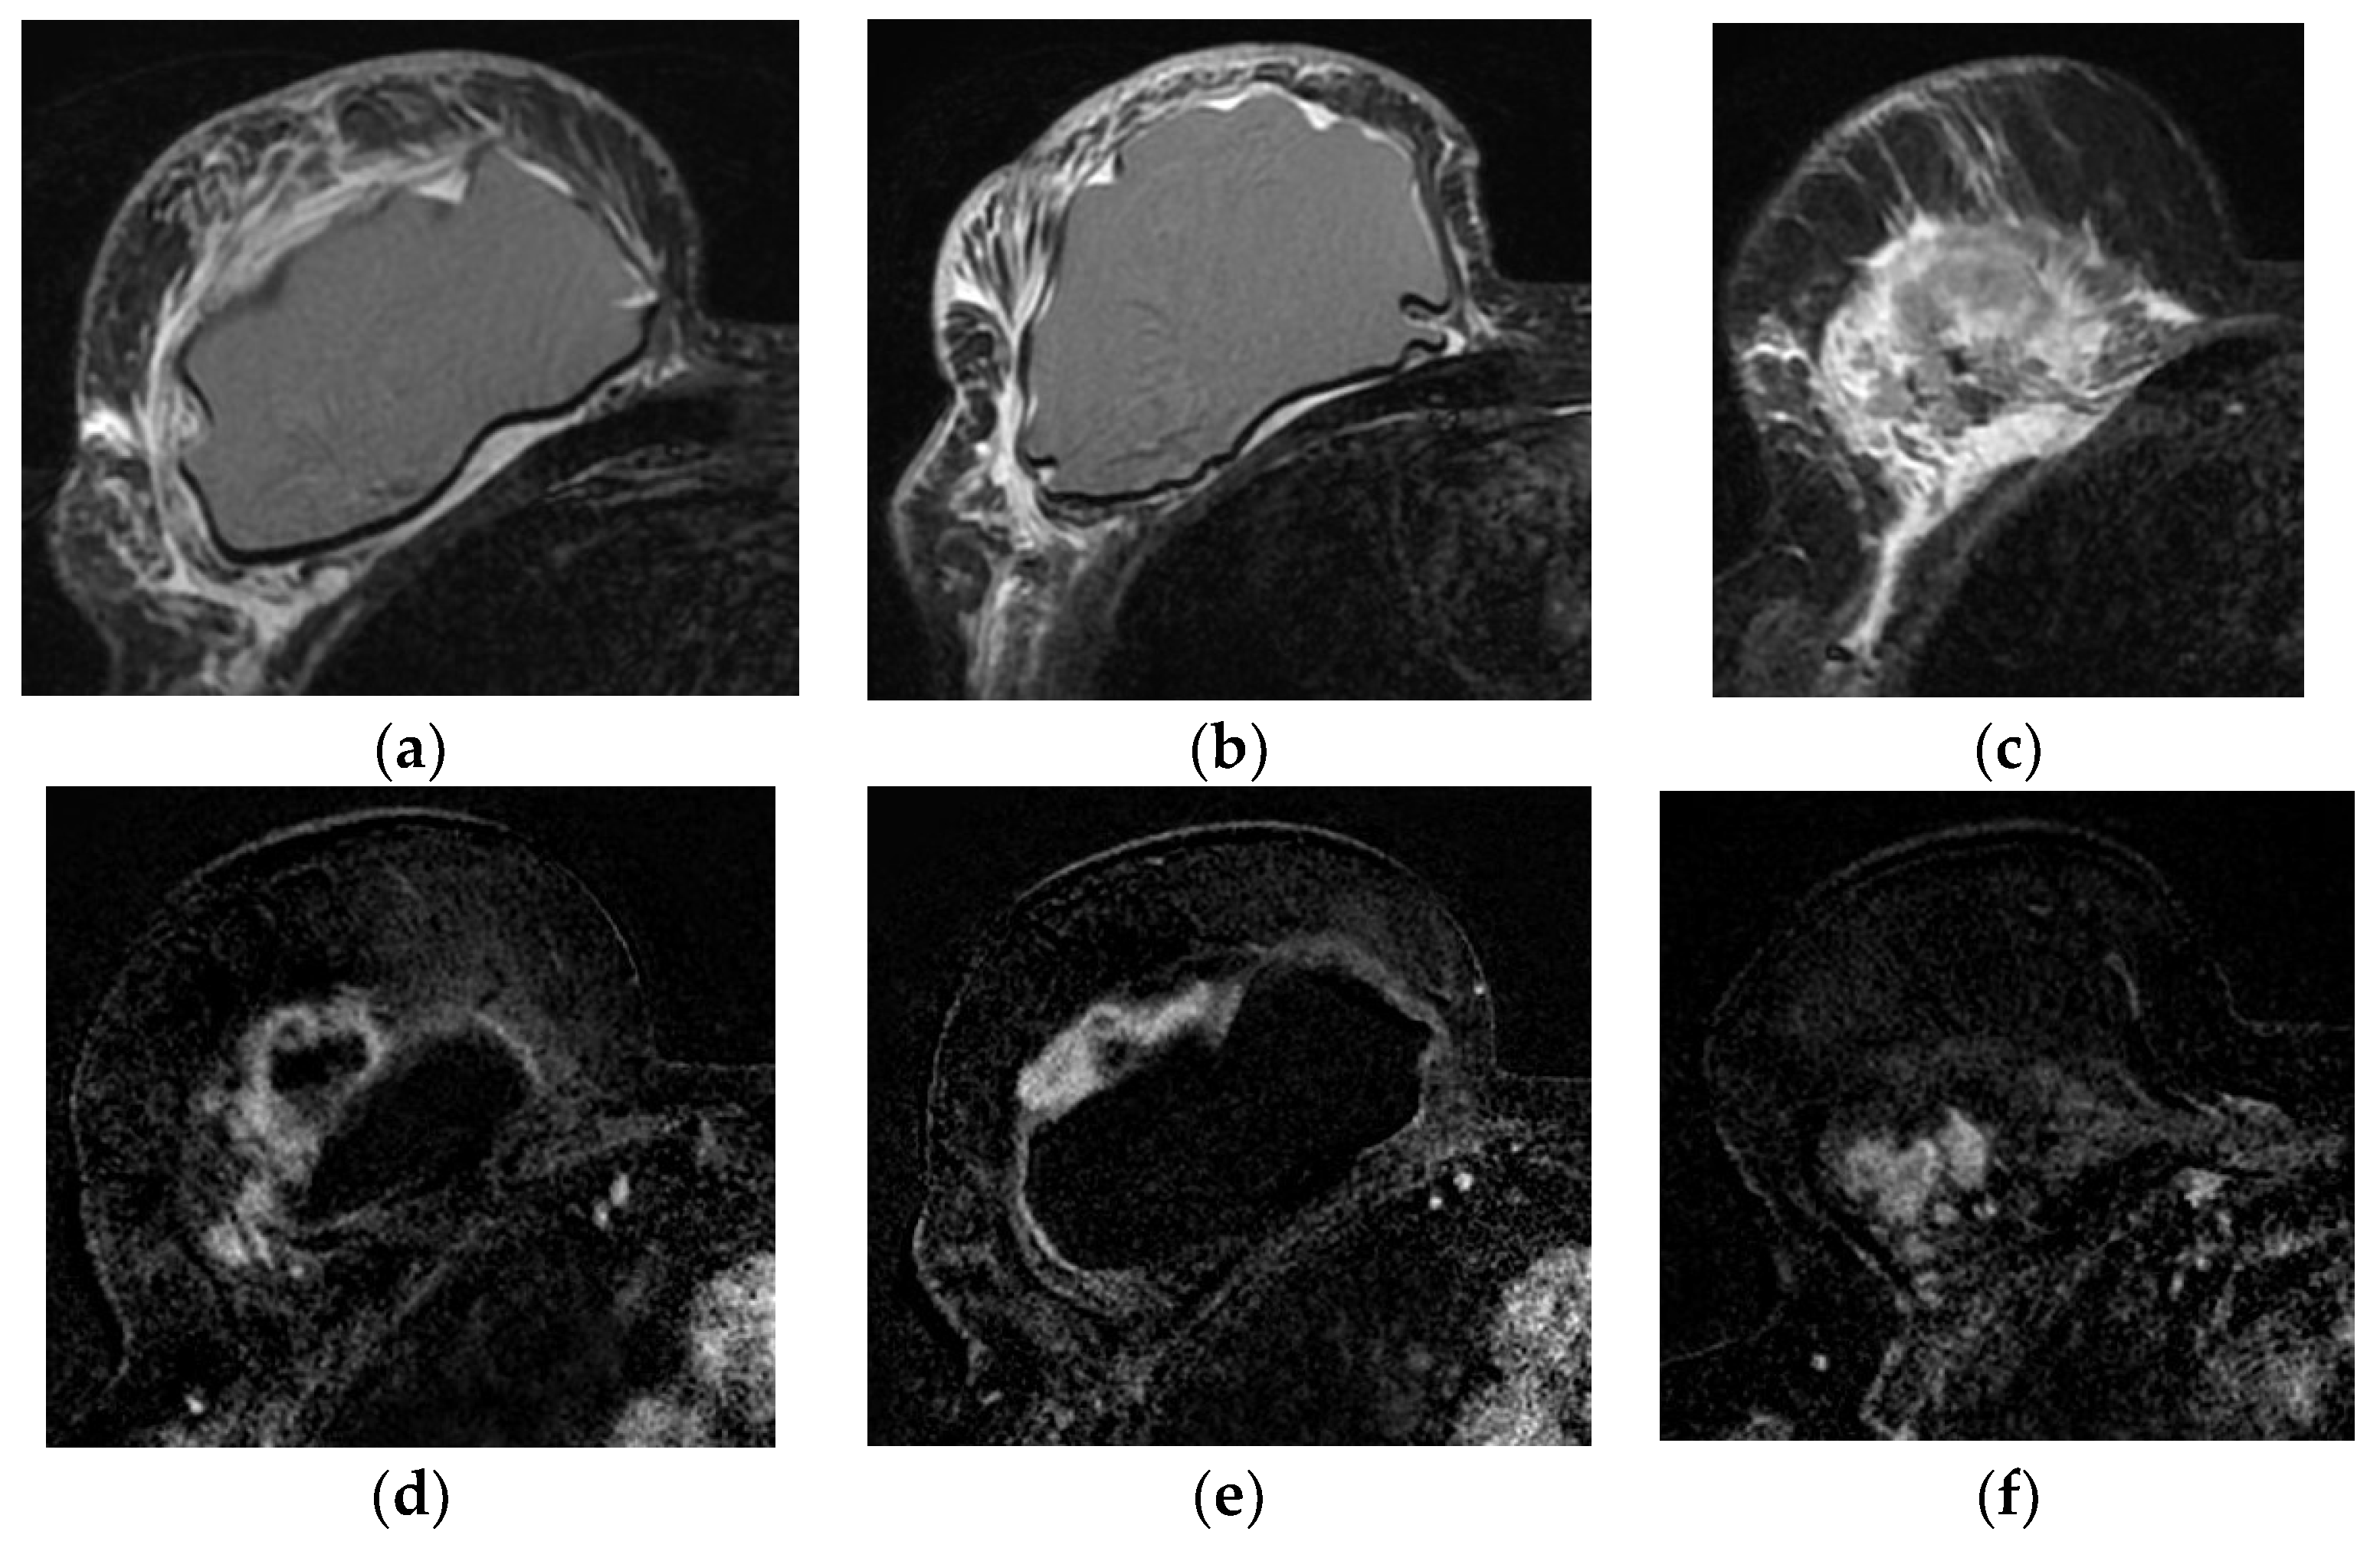

5.2.4. Capsular Contracture

- Grade I—normal soft tissues implant texture;

- Grade II—firm texture with normal contour;

- Grade III—firm texture with altered contour;

- Grade IV—firm texture with altered contour with concomitant pain [75].

5.2.5. Implant Rupture

- Wong, T.; Lo, L.W.; Fung, P.Y.; Lai, H.Y.; She, H.L.; Ng, W.K.; Kwok, K.M.; Lee, C.M. Magnetic resonance imaging of breast augmentation: A pictorial review. Insights Imaging 2016, 7, 399–410. [Google Scholar] [CrossRef] [PubMed]

- Norena-Rengifo, B.D.; Sanin-Ramirez, M.P.; Adrada, B.E.; Luengas, A.B.; Martinez de Vega, V.; Guirguis, M.S.; Saldarriaga-Uribe, C. MRI for Evaluation of Complications of Breast Augmentation. Radiographics 2022, 42, 929–946. [Google Scholar] [CrossRef]

- Soo, M.S.; Kornguth, P.J.; Walsh, R.; Elenberger, C.D.; Georgiade, G.S. Complex radial folds versus subtle signs of intracapsular rupture of breast implants: MR findings with surgical correlation. AJR Am. J. Roentgenol. 1996, 166, 1421–1427. [Google Scholar] [CrossRef] [PubMed][Green Version]

- Green, L.A.; Karow, J.A.; Toman, J.E.; Lostumbo, A.; Xie, K. Review of breast augmentation and reconstruction for the radiologist with emphasis on MRI. Clin. Imaging 2018, 47, 101–117. [Google Scholar] [CrossRef]